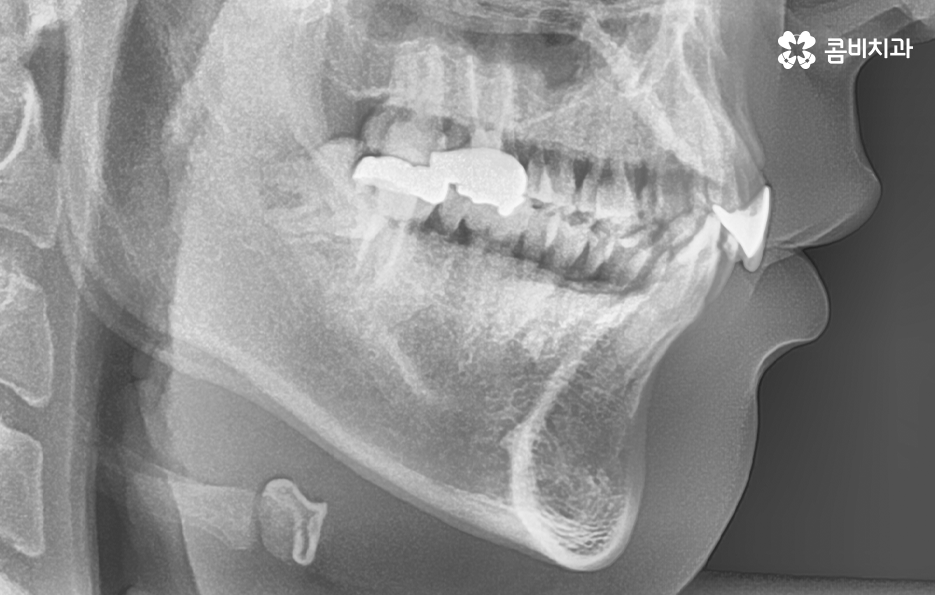

치아교정 계획은 기본적으로 치열과 교합, 골격과 얼굴형을 종합적으로 따져보고 치아교정 후의 변화 결과를 미리 잘 예측하여 치료 계획이 세워지고 있는데요

그렇기 때문에 치아교정에 대해 고민하신다면 자신의 상태를 먼저 3D CT 등으로 정확히 확인하시고 교정 전문의와 충분히 상의하셔서 자신에게 적합한 치료 계획을 1:1로 먼저 세워보시고 치료 목표를 먼저 세운 후에 하나씩 따져보시는 것이 가장 빠르고 정확한 치아교정 계획이 접근 방법이 될 거예요